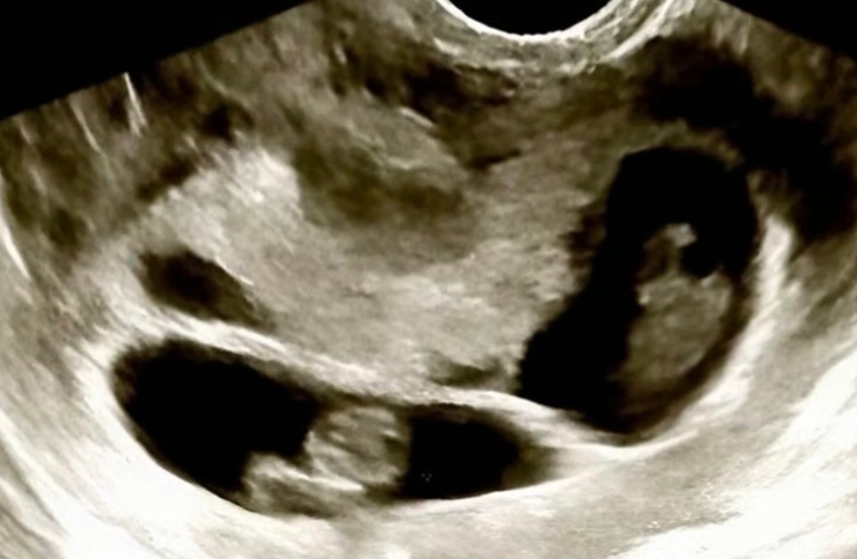

이후 두 사람은 지난 11월 멕시코에서 대리 출산으로 네 명의 아기를 얻었다는 영상을 공유하며 아이들의 성장을 기록할 것이라고 밝혔다. 린씨는 결혼 후 아이를 갖는 것이 오랜 꿈이었다고 덧붙였다.